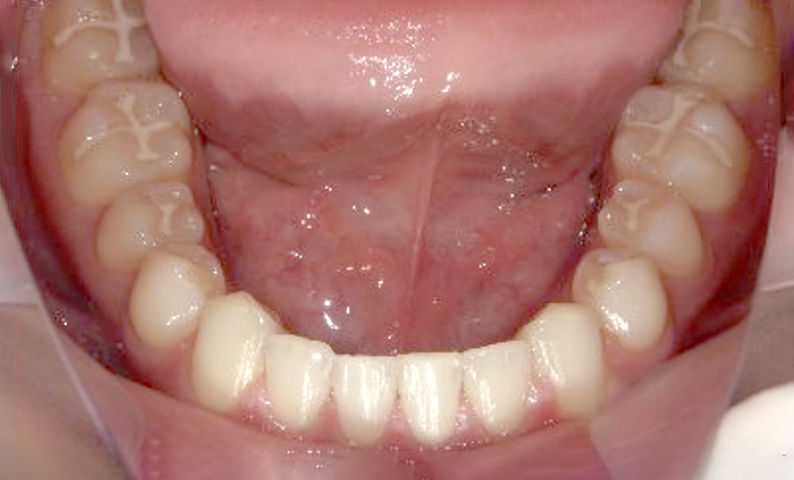

症例_001 前歯「すきっ歯」症例

治療期間:9ヶ月金額:51万円+税20代女性すきっ歯